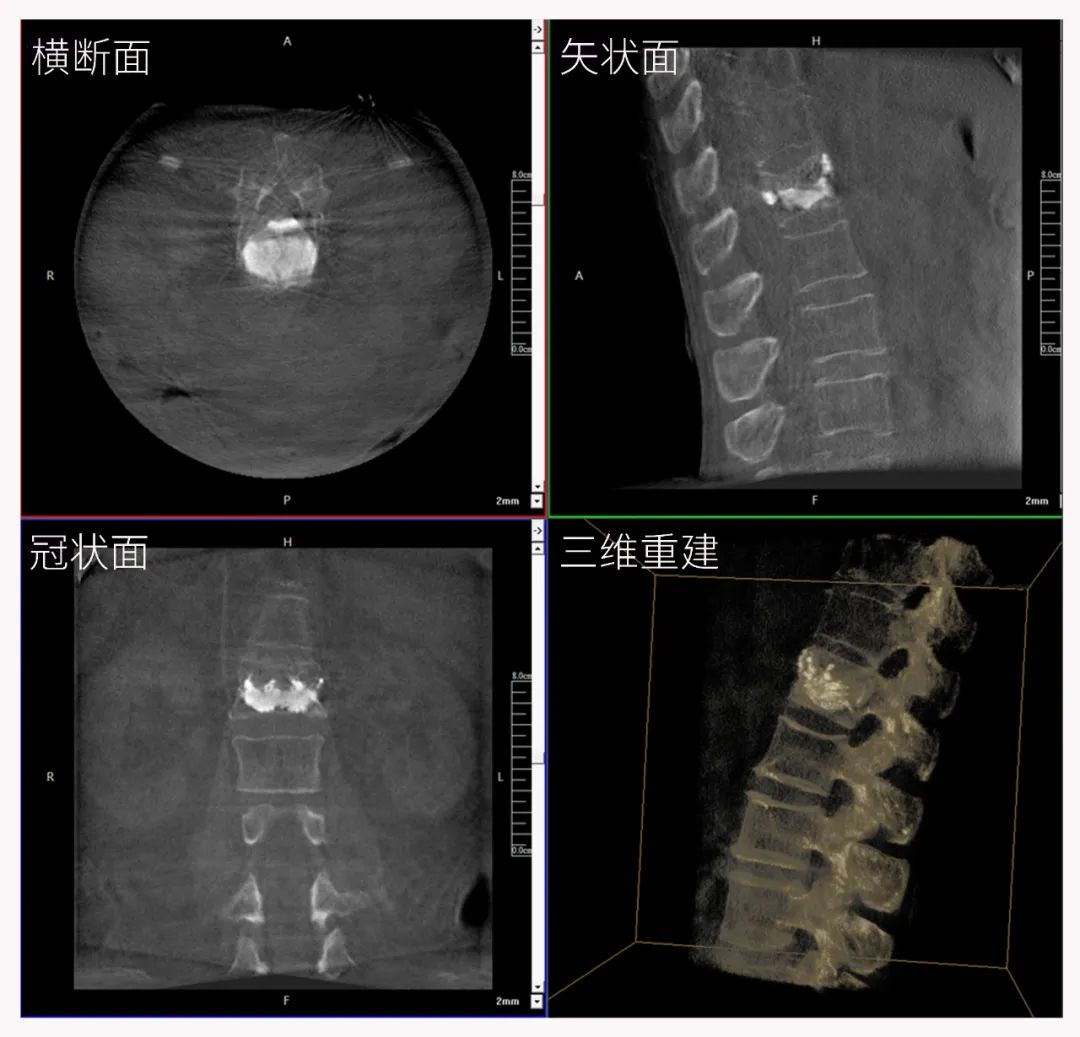

三維C形臂也被稱為“術中CT”,它具備二維C形臂的全部功能。此外,它還具備三維成像功能,三維C形臂旋轉采集多角度的二維投影數據,再通過計算機進行三維重建,能夠生成橫斷面、矢狀面、冠狀面斷層圖像以及三維立體圖像,提供更全面、更立體的解剖學信息。

三維“類CT”影像

三維切面影像可以看出病灶點

二維C形臂提供的影像存在固有局限性,其成像原理是基于單一方位的投影,導致深部解剖結構信息缺失,且容易受到骨骼和組織的重疊干擾,使得部分病灶難以清晰顯示,甚至被掩蓋。相比之下,三維C形臂通過三維重建技術,可以獲得類似CT的斷層掃描圖像,從而解決了二維影像的重疊問題。

醫生能夠利用這些三維圖像,更直觀、更深入地分析病變,進行全方位觀察,例如:精確評估骨折復位情況、清晰顯示內植入物的位置及其與周圍組織的關系等。尤其在復雜骨折、脊柱手術、呼吸介入等臨床場景中,三維C形臂提供的詳細信息對手術導航和療效評估至關重要。